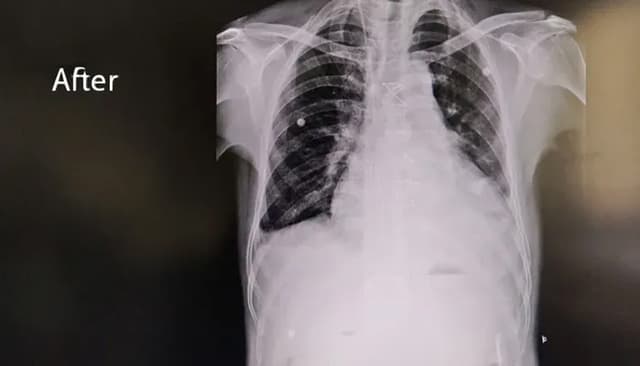

The Outcome: Recovery & Stabilisation

A Life Restored, A Heart Stabilised

- Rupture successfully repaired

- Hemodynamic stability restored

- Cardiac function normalised

- Recovery safe, steady, and complication-free